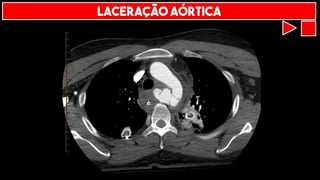

LACERAÇÃO AÓRTICA

TRANSECÇÃO AÓRTICA

PSEUDOANEURISMA AÓRTICO